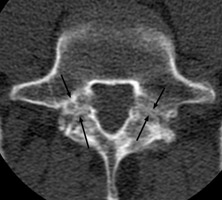

Incomplete Ring Sign

Spondylolysis

CT of the spine with discontinuity of the lateral bodies of the vertebrae with the posterior elements at the same level. This simple sign of discontinuity has been labeled the incomplete ring sign and is specific for fracture of the pars interartcularis (spondylolysis) as seen on CT scans. This sign is usually readily apparent because on no scan will the entire cortical ring be identified. Other causes such as spina bifida occulta can also appear as an incomplete ring, but with the discontinuity at a different site thereby making differentiation easy.

bulletLangston JW, Gavant ML: "Incomplete ring" sign: a simple method for CT detection of spondylolysis. J Comput Assist Tomogr 1985 Jul-Aug;9(4):728-9.          [See related articles]